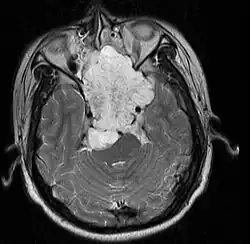

• Skull base:

• May be intracranial or extracranial, with mass effect symptoms depending on location

• Headaches and/or facial pain are common

• Pituitary insufficiency, hemianopsia/diplopia, cranial nerve deficits, nasal stuffiness.

• Maximal resection followed by proton beam irradiation.

• Overall survival is dependent upon local control of disease. Prognostic factor for local control of disease is amount of residual tumor after original surgery (<25cc residual tumor is better).

• Clear margins are achieved in <50% of skull base chordomas.

• Doses of 70 CGE necessary for control of residual disease.